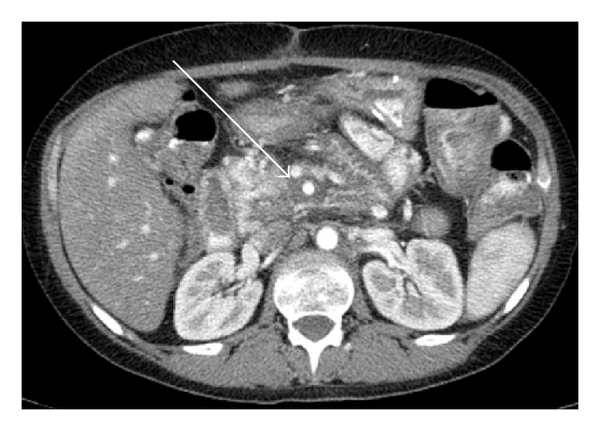

As Figures 1–5 demonstrate, the immediate postablation bed and zone are invariably larger than the original ablated tumor. We remain descriptive because the entire bed was extremely difficult to measure owing to the amorphous, irregular nature of the ablation. Moreover, the ablated tissue is not within an encapsulated organ; therefore, the ablation zone does not have defined borders as seen after, for instance, liver ablation. Four patients that showed continued stable disease are highlighted in Figures 1 through 4. An amorphous, hypoattenuating region with irregular shape persisted in subsequent CT scans in all patients with “stable disease.” Moreover, the ablation zone was typically smaller (due to decreased edema, hyperemia, and granulation tissue) than the immediate postablation bed in the following months and remained stable provided there was no recurrence. Imaging findings demonstrating recurrence are shown in Figure 5. Along with persistent irregular shape the ablation zone showed increased tumor bulk and extension as well as new mass effect (new narrowing of a blood vessel). Enhancement of the ablative bed was variable and often showed increased enhancement in the three-month and longer follow-up images. This was felt to be related to development of granulation tissue and fibrosis.

In our study, we found that the postablation bed is larger in volume than the initial mass. This is expected because it contains the tumor and the ablative margin. The postablation bed and zone appear irregular, amorphous, and hazy without margins or true boundaries. The ablation zone may decrease in size from the initial post-op bed to the initial surveillance study as the surrounding edema/fluid and inflammation resolve revealing the true ablation zone; however, as mentioned above, since there have been reports of an ongoing apoptotic process that persists up to 6–8 weeks after ablation, it will not be unusual to see some increase in volume in surveillance [19, 20]. Therefore, size is considered secondary in the CT evaluation for this reason and because the postablative bed/zone has poorly defined margins, making objective imaging assessment (size, attenuation) cumbersome. This may undoubtedly affect the accuracy and reproducibility of the measurement. Nonetheless, any increase in volume after stabilization of the postablation zone is considered worrisome for recurrence (Figure 5).